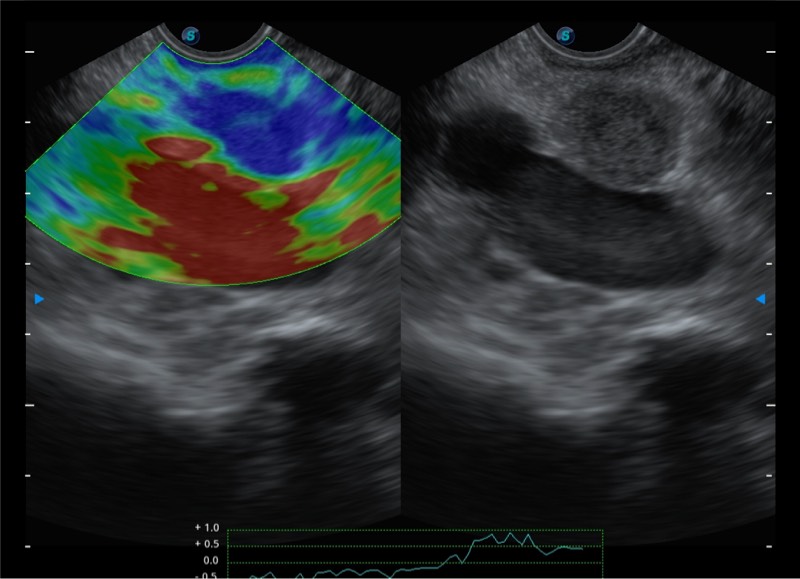

基于二十年的超声技术积累,云顶集团官网提供了最新一代的独立超声主机,在提供高质量图像的同时满足多学科使用。具备常见多普勒技术并提供弹性成像、声学造影等高端影像技术。新一代传感器具有更强的抗干扰能力并减少图像伪影。

150°超声扫描角度

4-12MHZ宽频输出